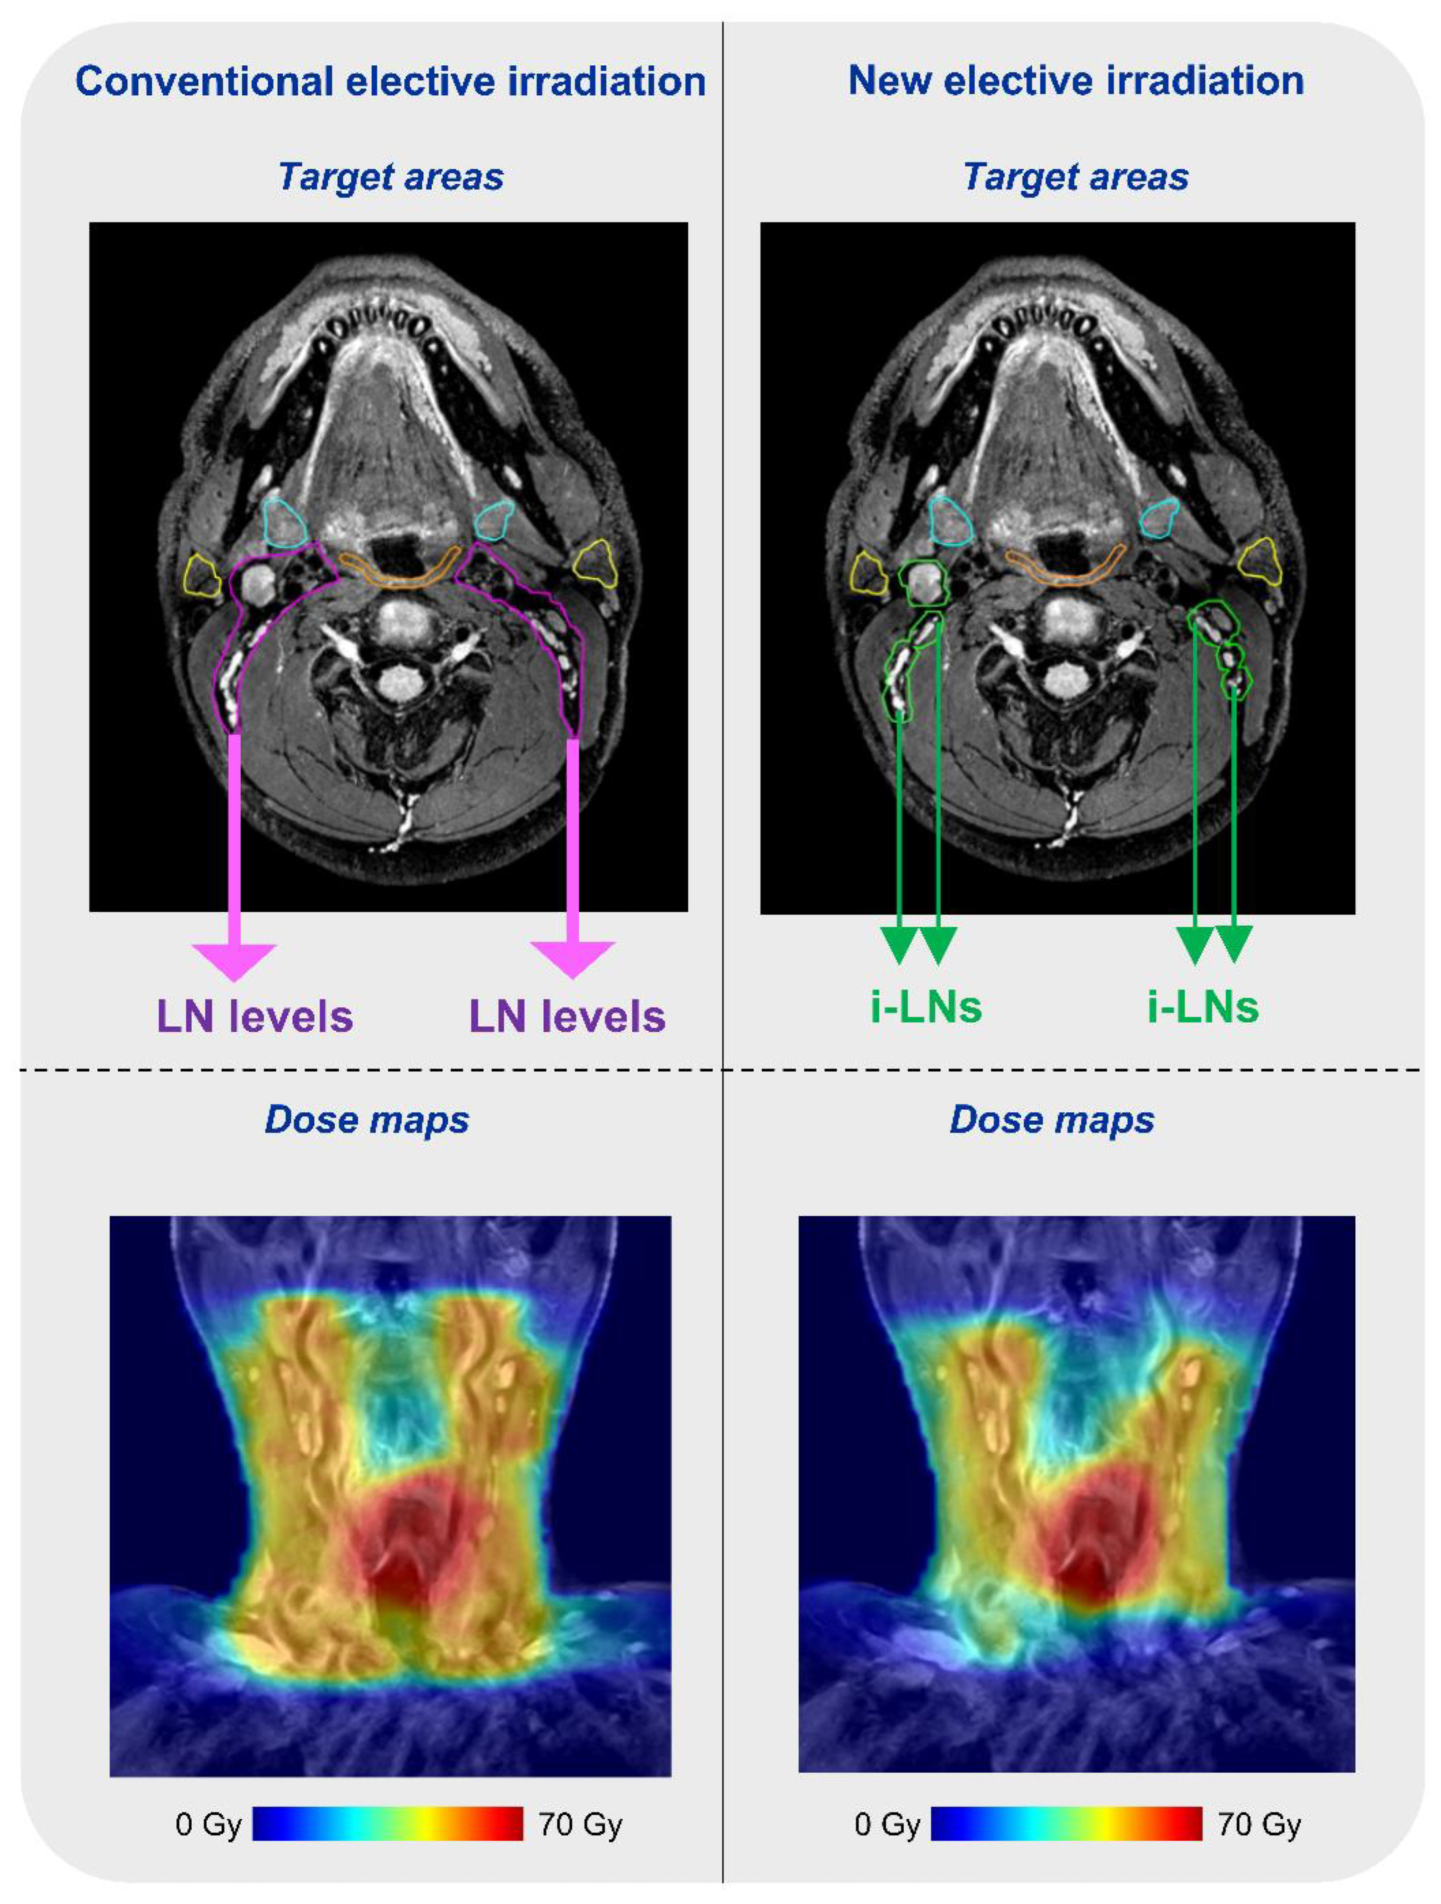

- Reinders, F.C.J.; Heijst, T.; Mases, J.; Terhaard, C.H.J.; Doornaert, P.A.H.; Philippens, M.E.P.; Raaijmakers, C.P.J. Magnetic resonance guided elective neck irradiation targeting individual lymph nodes: A new concept. Phys. Imaging Radiat. Oncol. 2021, 20, 76–81. [Google Scholar] [CrossRef] [PubMed]